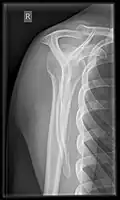

Fracture

Fractures of shoulder bones can include clavicular fractures, scapular fractures, and fractures of the upper humerus.

X-ray

Projectional radiography views of the shoulder include:

-

CR. shoulay film. -

Transaxillary conventional radiography -

Y-projection conventional radiography